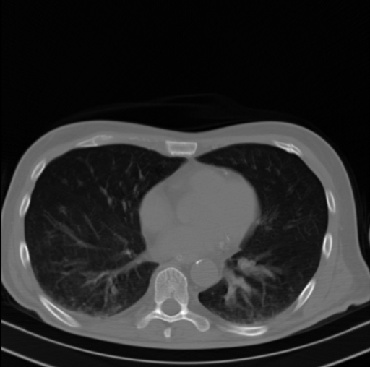

Early and reliable COVID-19 diagnosis based on chest 3-D CT scans can assist medical specialists in vital circumstances. Deep learning methodologies constitute a main approach for chest CT scan analysis and disease prediction. However, large annotated databases are necessary for developing deep learning models that are able to provide COVID-19 diagnosis across various medical environments in different countries. Due to privacy issues, publicly available COVID-19 CT datasets are highly difficult to obtain, which hinders the research and development of AI-enabled diagnosis methods of COVID-19 based on CT scans. In this paper we present the COV19-CT-DB database which is annotated for COVID-19, consisting of about 5,000 3-D CT scans, We have split the database in training, validation and test datasets. The former two datasets can be used for training and validation of machine learning models, while the latter will be used for evaluation of the developed models. We also present a deep learning approach, based on a CNN-RNN network and report its performance on the COVID19-CT-DB database.